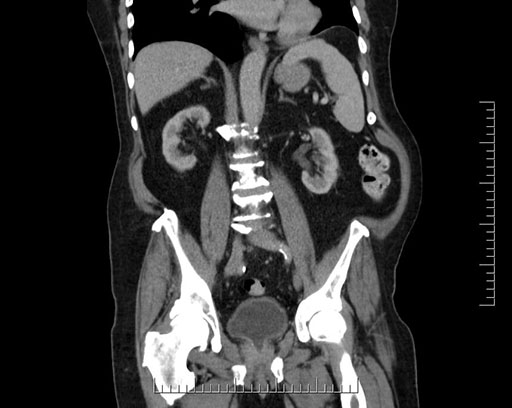

Whipple (pancreaticoduodenectomy) [case 7]

Look through the patient's CT scan to identify any areas of concern for the necessary procedure.

Coronal - stented

Imaging analysis

Based on your CT findings, which issue(s) would give reason for "planned slowing down moment(s)" in this case?

Considering a standard Whipple procedure, what step(s) of the operation would you do differently in this case?